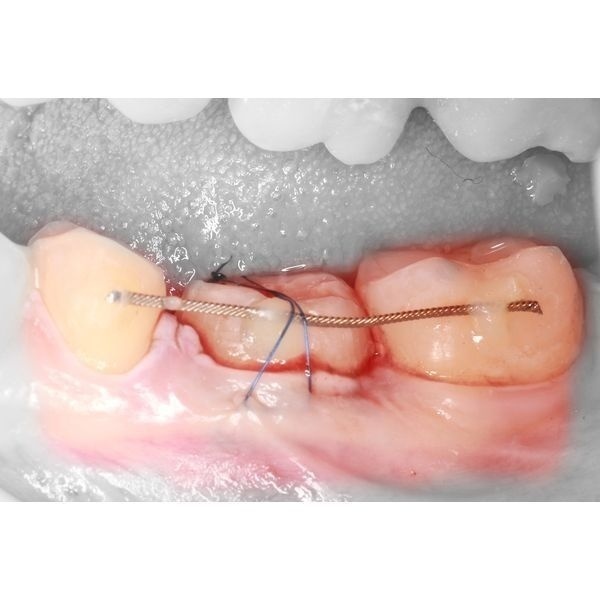

- специальными щипцами удалили зуб 2.8 и установили его на место зуба 4.6, после чего зафиксировали его ортодонтической проволокой-рейтейнером и жидкотекучим композитом;

- провели контрольную рентгенографию.

Операция длилась около 30 минут.